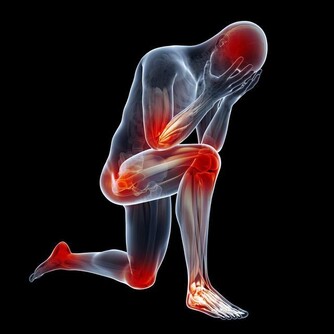

2、會陰疼痛

隨著癌細胞的轉移,前列腺癌患者會出現持續性的腰痛,還有會陰疼痛等。臥床時更為劇烈。

髖骨,胸腰椎是前列腺癌轉移的好發部位。常會有持續性,間歇性的疼痛,也有的人與有遊走的疼痛。